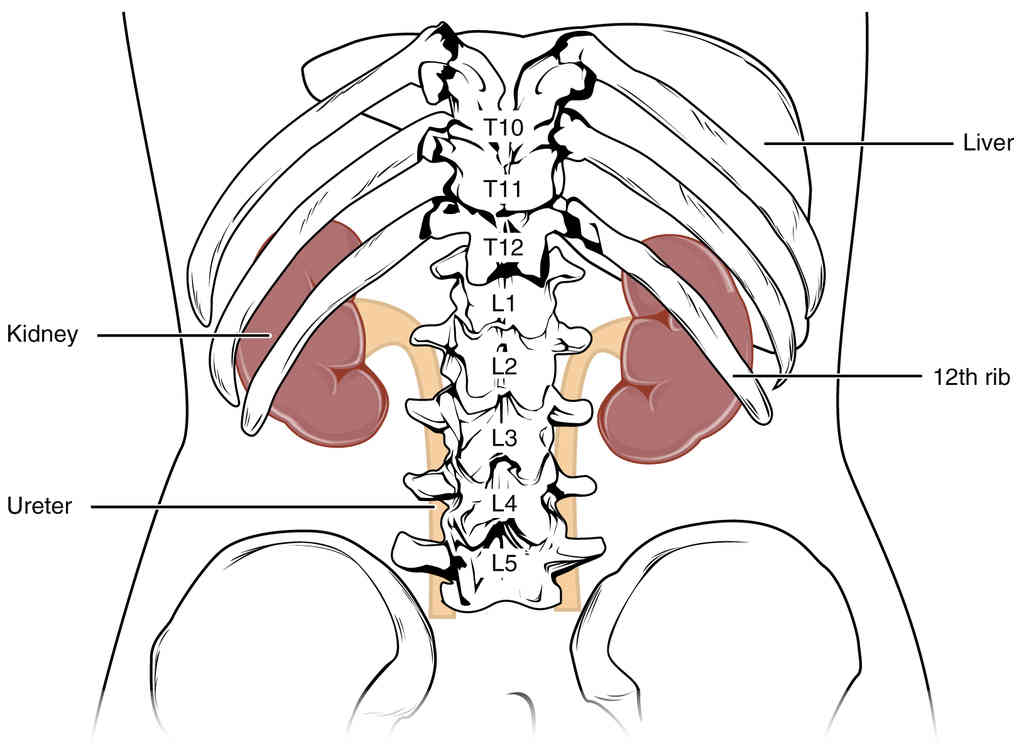

Anatomy, Physiology and Histology

This page is under construction. For now, it is just a resource of the images found in the OpenStax Anatomy and Physiology Handbook. It wil slowly change into a revision tool. Each slide has a number. Use this to refer to the slide. When completed, it will have an unlabelled section, with labelled slides in parallel. On the unlabelled slides, write your answer and use the labelled slide to assess yourself. Keep track by also noting the number on each slide. Improvement at each attempt is important, more so than full marks on a first attempt.